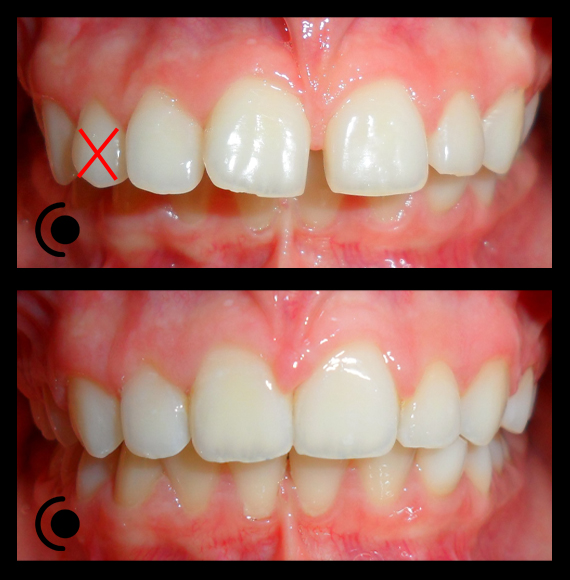

O našoj kvaliteti najbolje govore naši rezultati!